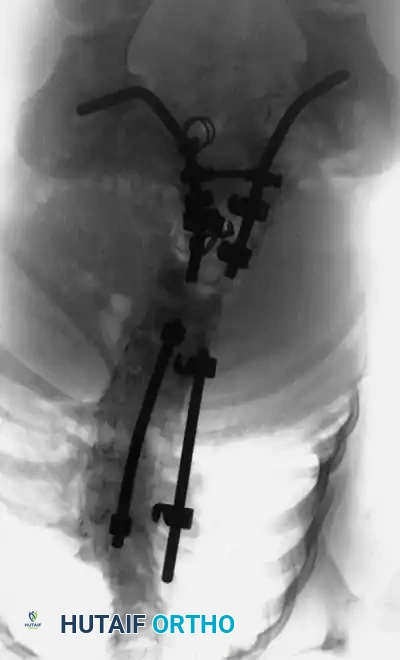

Image

Radiographic examples of progressive congenital curves requiring early intervention.